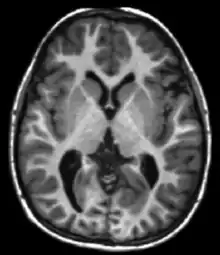

Neuroimaging

MRI is the investigative tool of choice for neurological cancers over CT, as it offers better visualization of the posterior cranial fossa, containing the brainstem and the cerebellum. The contrast provided between grey and white matter makes MRI the best choice for many conditions of the central nervous system, including demyelinating diseases, dementia, cerebrovascular disease, infectious diseases, Alzheimer's disease and epilepsy.[30][31][32] Since many images are taken milliseconds apart, it shows how the brain responds to different stimuli, enabling researchers to study both the functional and structural brain abnormalities in psychological disorders.[33] MRI also is used in guided stereotactic surgery and radiosurgery for treatment of intracranial tumors, arteriovenous malformations, and other surgically treatable conditions using a device known as the N-localizer.[34][35][36] New tools that implement artificial intelligence in healthcare have demonstrated higher image quality and morphometric analysis in neuroimaging with the application of a denoising system.[37]